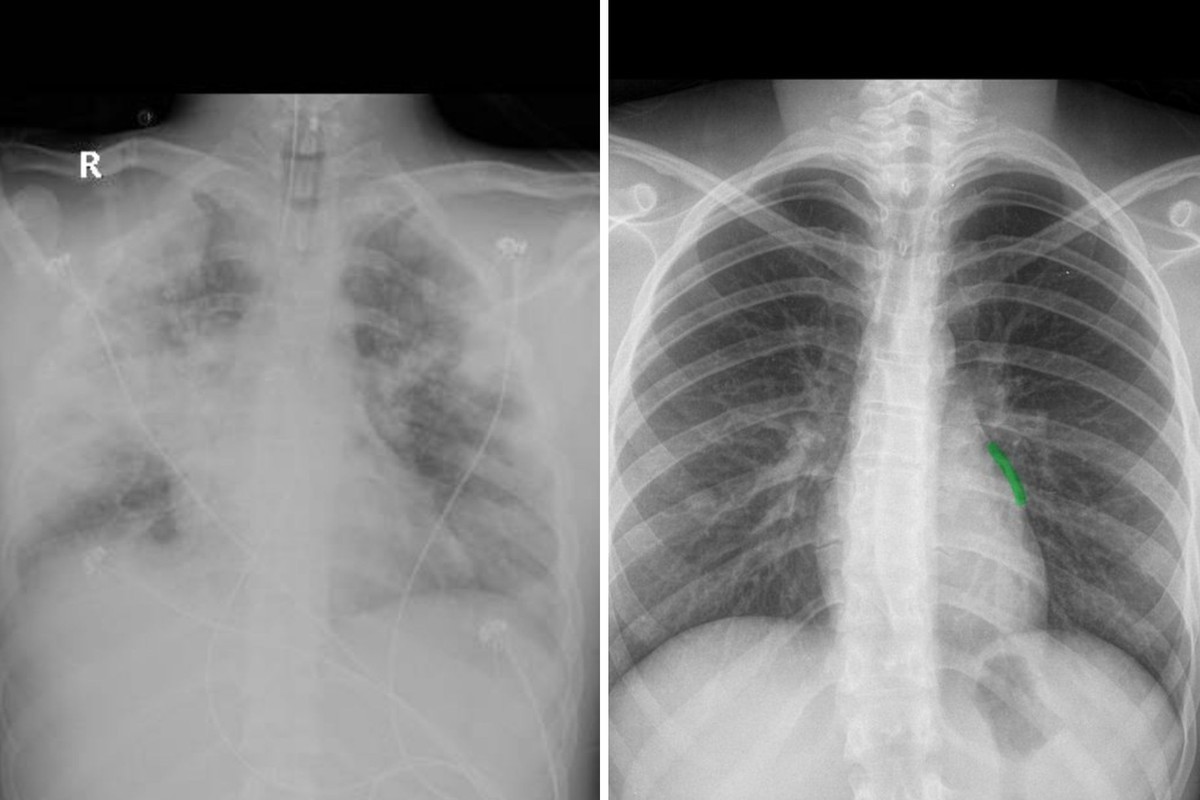

【国内新闻编辑部讯】根据globo 10月16日报道报道,一位名叫莉娅·佩瓦的母亲公开了她已去世儿子的肺部X光片,揭示了电子烟对健康的潜在危害。莉娅透露,儿子自15岁开始使用电子烟,其肺部X光片显示出明显的白色炎症,尽管电子烟并非儿子20岁去世的直接原因,但其对肺部的损害严重影响了儿子抵抗感染的能力。

巴西内科协会桑保罗呼吸病学协会成员弗雷德·费尔南德斯医生分析,X光片显示的肺损伤可能与电子烟使用相关,即所谓的evali,这是一种导致气体交换受限的严重炎症反应。